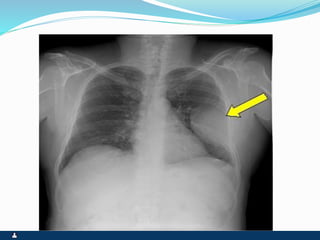

PNEUMOTÓRAX

RUPTURA DE UM DOS FOLHETOS

SINTOMAS SINAIS

 PRIMÁRIO ( ESPONTÂNEO

) SECUNDÁRIO(

TRAUMA,IATROGÊNICO )

 INÍCIO SÚBITO

 DOR PLEURÍCA INTENSA

 TOSSE SECA

 DISPNÉIA

 FACIES DE DOENÇA

AGUDA,ANSIEDADE E

SUDORESE

 EXPANSIBILIDADE REDUZIDA

 DESVIO CONTRALATERAL DO

MEDIASTINO

 ABAULAMENTO

HOMOLATERAL DOS

ESPAÇOS INTERCOSTAIS

 FTV ABOLIDO

 TIMPANISMO

 MV ABOLIDO

 RUIDOS ADVENTÍCIOS

AUSENTES

 ENFISEMA SUBCUTÂNEO

EVENTUAL